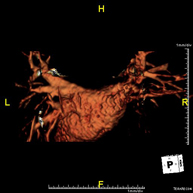

Prueba diagnóstica no invasiva que consiste en la obtención de imágenes de alta definición anatómica de todo el cuerpo mediante el empleo de un campo electromagnético y ondas de radio (con un emisor y un receptor). No utiliza radiación ionizante. Es una prueba muy importante en la búsqueda de metástasis en pacientes con neoplasia conocida. No requiere preparación previa. No es necesario el empleo de contraste paramagnético (Gadolinio). - Angio-RM Aorta abdominal

Prueba diagnóstica no invasiva que consiste en el estudio de la arteria aorta abdominal, obteniendo imágenes de alta definición anatómica mediante el empleo de un campo electromagnético y ondas de radio (con un emisor y un receptor). Es indispensable el uso de contraste paramagnético (Gadolinio). Sin embargo, no utiliza radiación ionizante. La calidad de las imágenes permite realizar reconstrucciones en 2D y 3D. Está indicado en aquellos pacientes con enfermedad vascular (aterosclerosis), estudio de aneurismas, en estudios pre-quirúrgicos de lesiones adyacentes a la aorta abdominal como "mapa" vascular, etc. - Angio RM Aorta-ilíaca

Prueba diagnóstica no invasiva que consiste en el estudio de la arteria aorta abdominal de las arterias ilíacas, obteniendo imágenes de alta definición anatómica mediante el empleo de un campo electromagnético y ondas de radio (con un emisor y un receptor). Es indispensable el uso de contraste paramagnético (Gadolinio). Sin embargo, no utiliza radiación ionizante. La calidad de las imágenes permite realizar reconstrucciones en 2D y 3D. Esta prueba está especialmente indicada como estudio pre-quirúrgico (mapa vascular) antes de intervenciones percutáneas o quirúrgicas de aorta abdominal y arterias ilíacas, estudio complementario en pacientes con isquemia de miembros inferiores, etc. - Angio RM Arterial extremidades inferiores